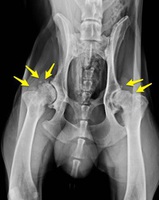

Una vez el veterinario, por medio de la anamnesis y el examen físico tiene la sospecha de una artrosis, la prueba más sencilla para confirmarlo es una RADIOGRAFÍA.

Los signos radiológicos de artrosis (puede tener uno, varios o todos) son:

- Efusión sinovial ( derrame articular)

- Presencia de osteofitos ( áreas de hueso inmaduro que se aprecian en la radiografía como perlitas de hueso o como irregularidades en el contorno de la articulación)

- Esclerosis subcondral ( líneas blancas en el hueso adyacente a la articulación)

- Disminución del espacio articular por erosión del cartílago